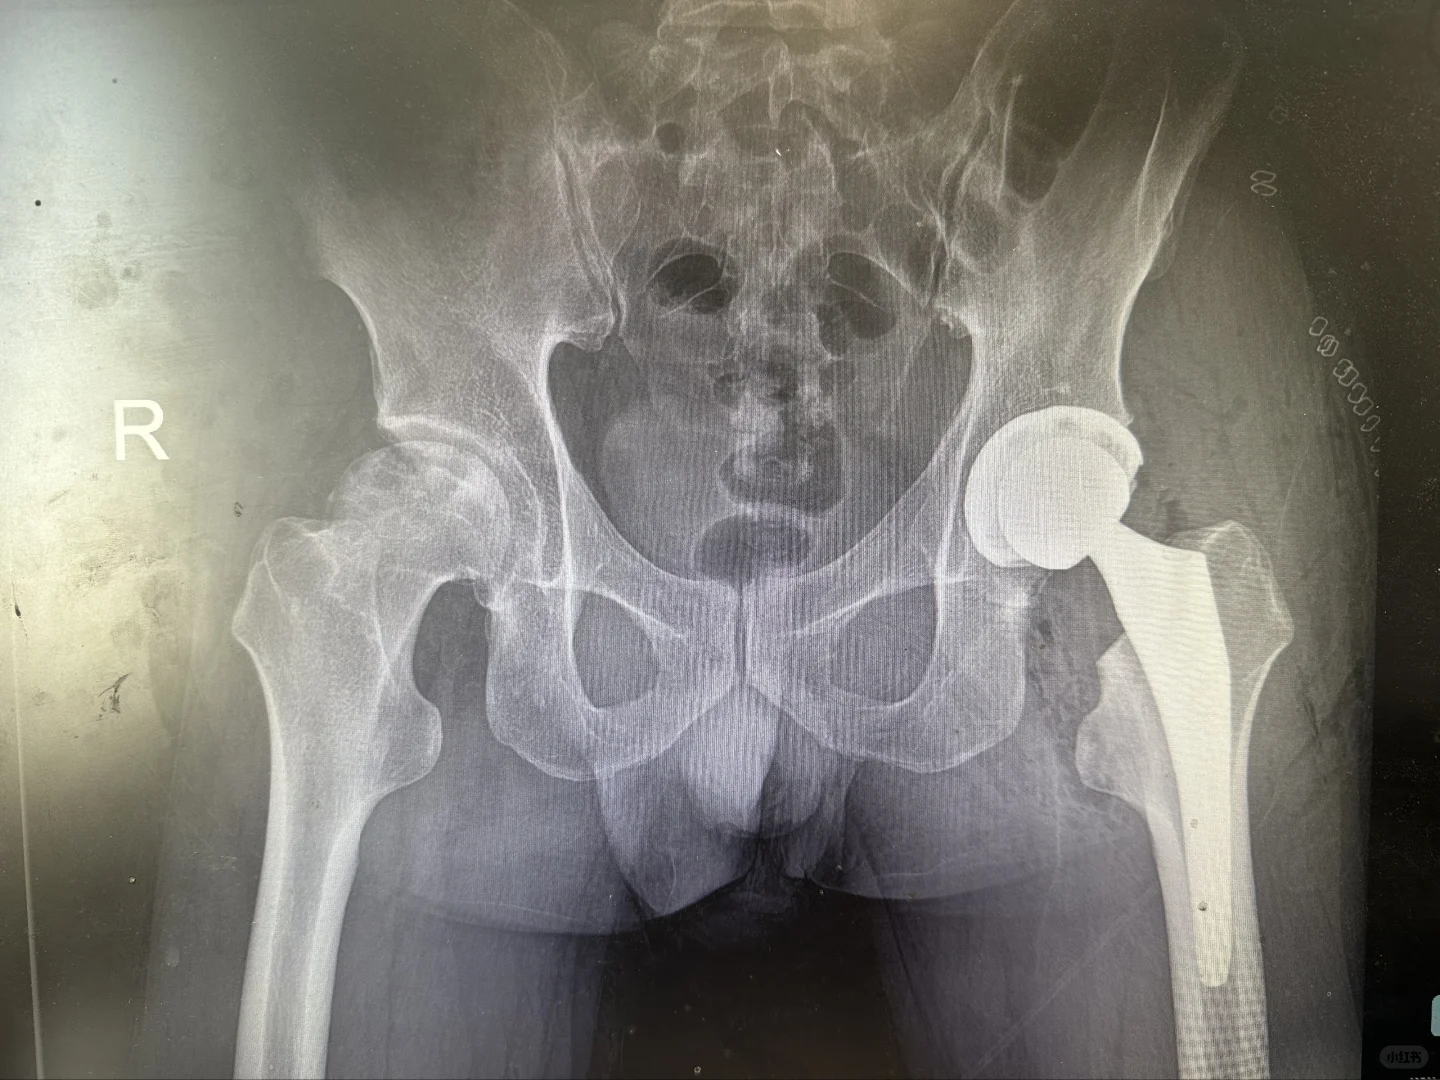

关节置换

髋膝关节置换手术是二十世纪以来最成熟的手术,1小时的手术时间能够给患者带来关节的重生,从此告别让人无法忍受的疼痛,回归正常生活,老人上下楼梯爬山跳舞不是梦。

给大家看看我们的手术器械和术后影像,抡大锤的马医生在线回复您的疑问,点个关注,持续解答。